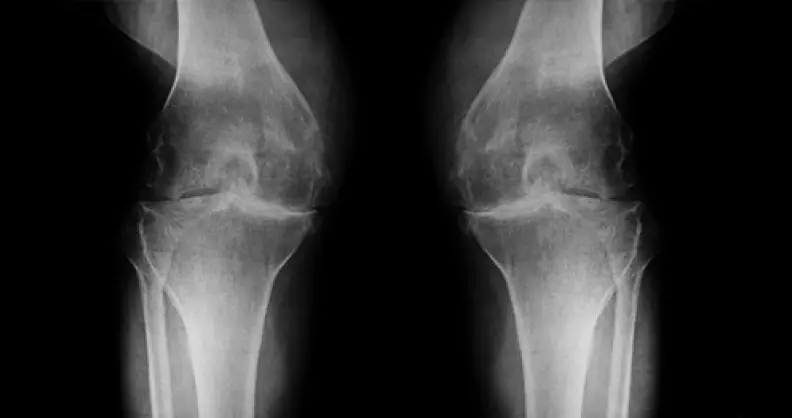

En 2025, ma femme Aminata a reçu un diagnostic d'arthrose du genou. Je dois admettre que ces moments ont été très durs et ont marqué un tournant dans ma vie. Depuis 2 ans nous avons tout tenté pour guérir ma femme : exercices de kinésithérapie, refus de faire de l'exercice, prise de vitamines et compléments alimentaires divers (chondroïtine, glucosamine, MSM, etc.), gels, Géluless.